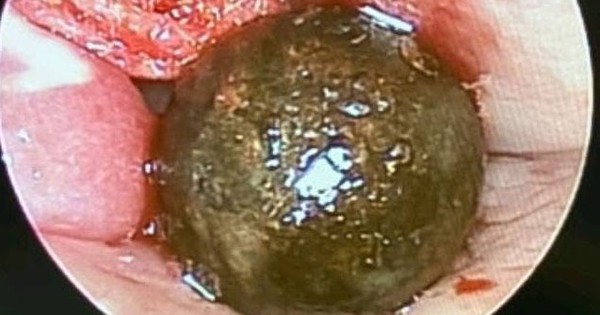

Thường xuyên ăn món tái, nam thanh niên bị sán chui qua hậu môn trong lúc ngủ